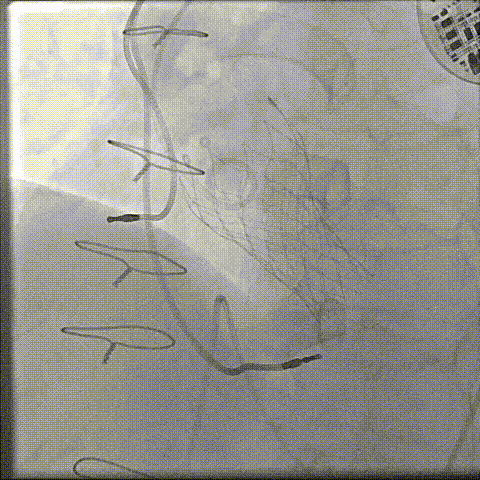

器械过弓柔顺